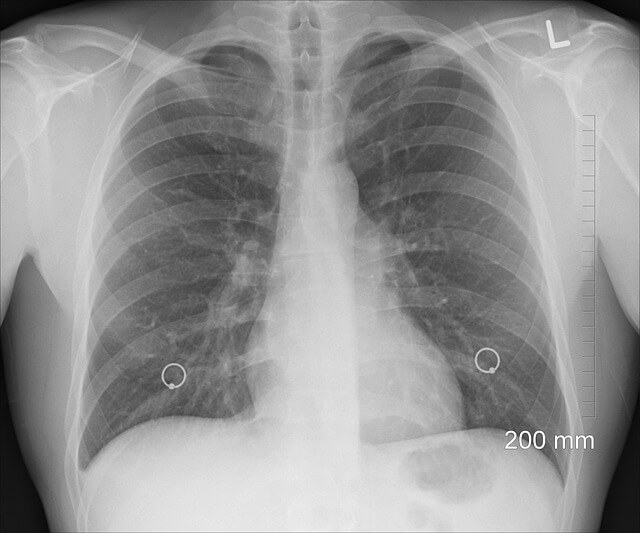

흉부촬영

마이코플라즈마 폐렴의 가능성에 대해 판단할 때 제일 빠르게 알 수 있는 방법 중 하나입니다

폐렴이란 이름처럼 엑스레이에서 폐아랫부분에서 집중적으로 발견되는 점이 있습니다